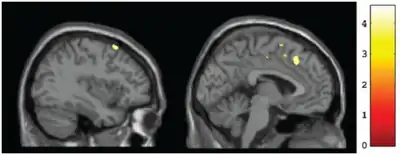

Structural abnormalities of the brain are observable, physical damage to the brain or brain structures caused by prenatal alcohol exposure. Structural impairments may include microcephaly (small head size) of two or more standard deviations below the average, or other abnormalities in brain structure (e.g., agenesis of the corpus callosum, cerebellar hypoplasia).[16]

Microcephaly is determined by comparing head circumference (often called occipitofrontal circumference, or OFC) to appropriate OFC growth charts.[22] Other structural impairments must be observed through medical imaging techniques by a trained physician. Because imaging procedures are expensive and relatively inaccessible to most people, diagnosis of FAS is not frequently made via structural impairments, except for microcephaly.

Evidence of a CNS structural impairment due to prenatal alcohol exposure will result in a diagnosis of FAS, and neurological and functional impairments are highly likely.[2][16][21][24]